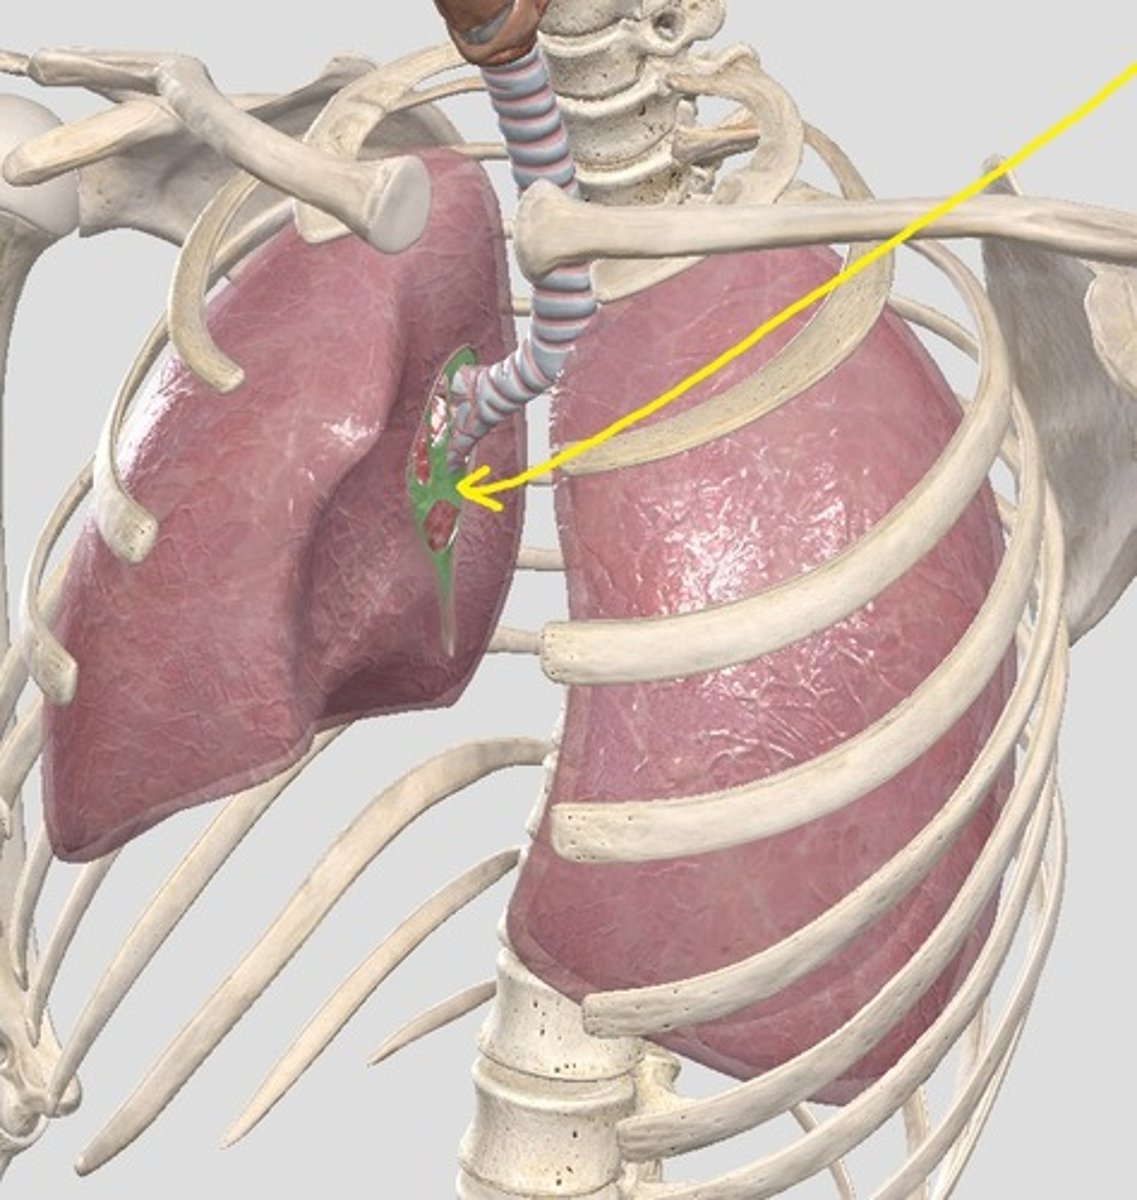

base (diaphragmatic surface)

apex

hilum of right lung

right main bronchus

left main bronchus

lobar bronchi